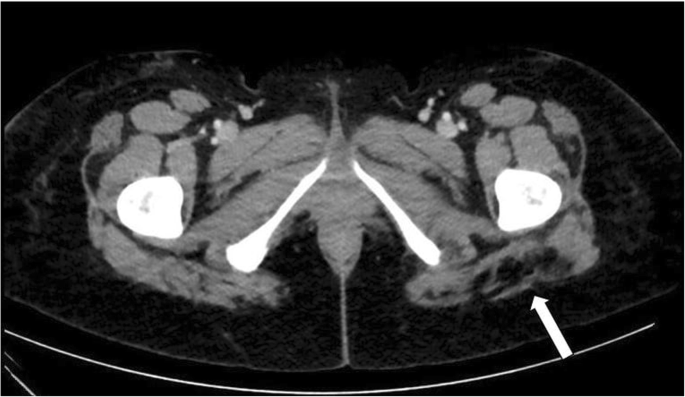

Post-operative computed tomography (CT) in our institution revealed distension of the inferior aspect of the left Gluteus Maximus muscle with fat in an area adjacent to the sciatic nerve (Fig. 1). The involved aspect of the left Gluteus Maximus was 1.7 times the thickness of the right side. The remainder of the study revealed edema in the remaining areas of the posterior thighs and abdomen consistent with standard post-liposuction changes. NCV studies of the lower extremities indicated the absence of posterior Tibial F-responses and posterior Tibial H-reflex on the left side compared to normal responses on the right side (Fig. 2). Based on these findings, it was concluded that the patient suffered from an acute left sided sciatic nerve lesion above the bifurcation in the area of the buttocks.

Computed tomography (CT) image of the lower gluteal region of the patient in case 2. White-colored areas correspond to the bones. The white arrow indicates areas of low attenuation (black) corresponding to significant fat within the inferior aspect of the left Gluteus Maximus muscle adjacent to the sciatic nerve (SN)

Scenarios similar to our case 2 have only been reported by Cardenas-Mejia et al. and Vasilakis et al. as recently as 2009 and 2018, respectively. The former reported a bilateral sciatic nerve axonotmesis in a patient after grafting only 200 cc of fat in each buttock, with most of the volume injected in the Gluteal muscles [15]. Vasilakis also reported on a bilateral case of sciatic neuropathy, following gluteal augmentation, with only partial recovery on one side after more than one year of physical therapy [5]. In both cases, electroneurography and imaging revealed direct compression and/or trauma to the sciatic nerve. While the second patient in our report was showing signs of clinical improvement, CT imaging revealed likely compression, and possibly direct trauma, as evidenced by fat distension adjacent to the sciatic nerve sheath (Fig. 1).